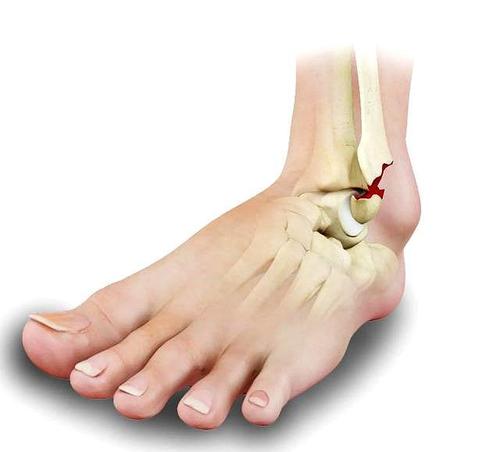

踝关节骨折

脚踝骨折图片

踝关节骨折分型图片